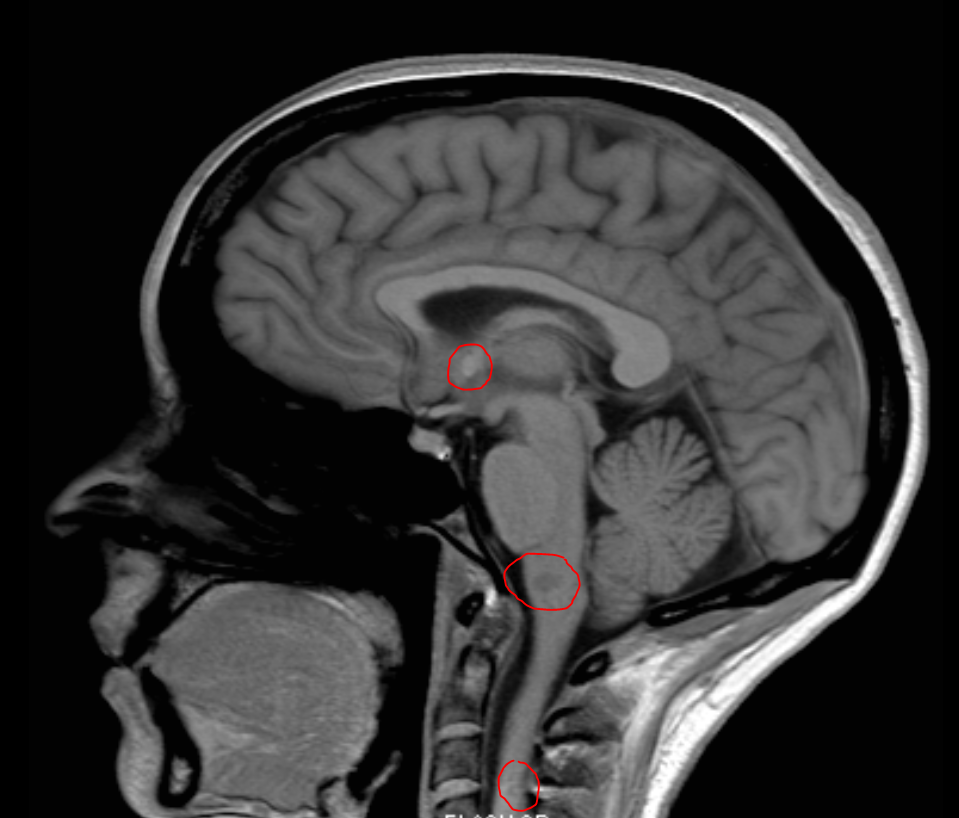

The end of 2013 was not much fun. This is my brain:

You will notice faint marks (helpfully circled in red). These are lesions or scars caused by my immune system savagely attacking my central nervous system. Arsehole! The fateful diagnosis.. Multiple Sclerosis. What a shocker.. stopped Fun Times right in their tracks. Sucks right.

Well yes and no. A year and bit later, while still lesioned and tingly (read up if you want) I am fitter, healthier, slimmer and happier. So screw you immune system, Fun Times are back on the menu.